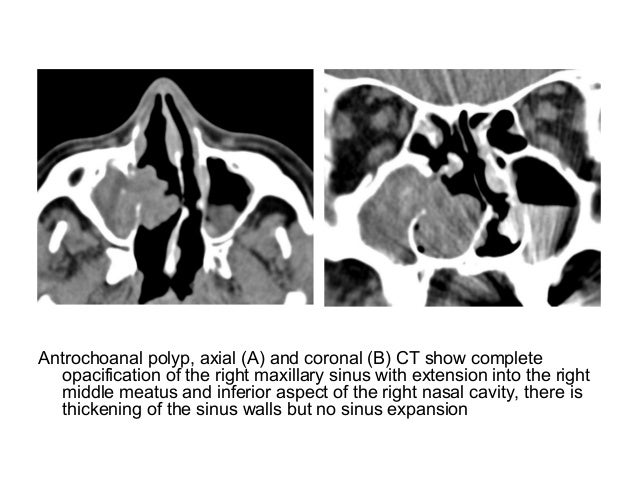

The dangers of focal tooth infections. The dangers of focal enamel infections. Introduction in current years there has been a reawakening of the risks of oral infections and their ability. What is general opacification of the maxillary sinus? Ehow. What is overall opacification of the maxillary sinus?. The maxillary sinus is the hollow space at the back of your cheeks, very close to your nose. When a ct scan is taken of the. Aplasia and hypoplasia of the maxillary sinus a case collection. Maxillary sinus aplasia and hypoplasia are uncommon conditions that may reason signs and symptoms which includes complications and voice alteration. Most of the people of patients are asymptomatic. We did now not discover effects for bilateral maxillary paranasal sinus ailment. Paranasal sinus irritation and non springerlink. Paranasal sinus irritation and nonspecific orbital inflammatory syndrome an unusual association. Endoscopic sinus surgical operation for maxillary sinus mucoceles. · maxillary sinus mucoceles are rather rare among all paranasal sinus mucoceles. With the introduction of endoscopic sinus surgical techniques. Bilateral aplasia of paranasal sinuses springerlink. Paranasal sinus anatomical anomalies with unknown etiology are commonplace. Maxillary and/or frontal sinus aplasia or hypoplasia are more common than the other types. Paranasal sinus infection and non springerlink. Paranasal sinus inflammation and nonspecific orbital inflammatory syndrome an uncommon affiliation.